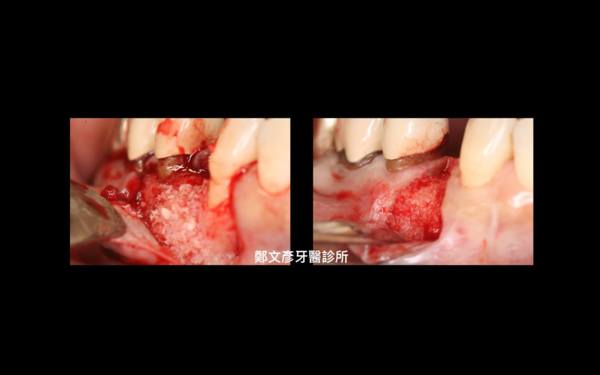

Role of granulation tissue in socket preservation

3. Role of granulation tissue in socket preservation